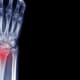

Distal radius fractures remain one of the most common injuries encountered in orthopedic practice. Yet for many physicians, managing these fractures in older adults has become increasingly nuanced — particularly as patient expectations and activity levels continue to rise.

“As physicians, our practices evolve,” says Roy Cardoso, M.D., orthopedic surgeon with Baptist Health Orthopedic Care. “I started my career focused on high-energy trauma. Now I see a large number of wrist fractures in active older adults with osteoporosis.”